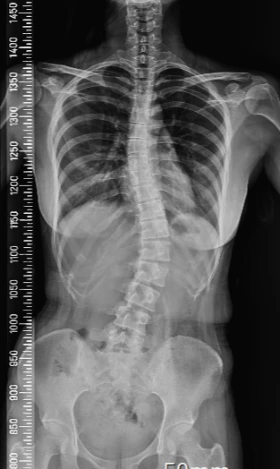

선천적인 체질에 어려서 당했던 가정폭력의 후유증과 소녀가장 신분에 여의치않아서 돌볼 수 없었던 시간까지- 복합적인 이유로 신경질환계의 전신에 통증을 앓는 지병이 있다. Fibromyalgia Syndrome, *섬유근통증후군이다.

폭력의 후유증으로 척추가 휘고 돌아갔기 때문인줄 알았다.

섬유근통증후군을 대부분이 복합적 합병을 갖고 있고 우울증을 가지고 있다. 그래서 호전되게 하려면 환자의 상태와 체질에 따라 다방면의 치료를 병행해야한다. 심리 치료 및 항우울 약물치료, 바닥난 체력과 통증에 부담되지않을 전문가의 1:1 재활치료, 긴 시간을 투자해서 차근차근 환자마다 맞는 치료법과 약물을 실험해야 한다. 내 경우엔 통증을 일시적으로 완화시키는 체형과 통증 치료에만 월 최소 50~100만원 이상 들어갔다. 무엇보다 일시적인 치료였으니까, 꾸준히 가야만 하루이틀 덜 아팠고, 병원을 다녀오는 일과와 재활과정에서온 피로로 근로가 우선이었던 나는 점심시간을 내어주고 그 시간에 치료를 받고 아버지로부터 받은 가정폭력덕에 척추가 돌아간 문제도 있어 마침 소화가 잘 안 되었으니 식사도 거르게 되었다. 당연히 몸무게는 쭉쭉 빠져나가서 살을 찌워야된다는 말 역시 의사선생님에게 들었다.

이후에 조금 급여가 안정적이게 되었을 때 희망에 차서 제일 크고 유명한 병원들에 가고 원장 특진을 예약받아 당장 수술비와 입원비, 회복 기간에 대한 여유는 없지만 알아보았었다. 월 최소 150만원 정도를 투자해 예후와 경과를 봐야하니 내게 맞는 치료법을 함께 찾아가보자고 했다. 섬유근통증후군을 낫게 하기 위한 것중에 하나로 돌아가고 휜 척추뼈를 못들로 꼿꼿하게 교정하는 큰수술을 해야한다고 말하면서도, 수술비는 수천만원에 회복기간만 최소 반년, 후유증으로 목이나 골반뼈가 돌아갈 것이고 허리를 쓰기 힘들 것이라 했다. 난 여전히 소녀가장에서 나이 4살 더 먹고 저축할 겨를 없이 빠듯하게 살아온 상태였다. 급여가 150여만원에서 좀 올랐다고 신나서 찾아가봐야 절망할 뿐이었다.